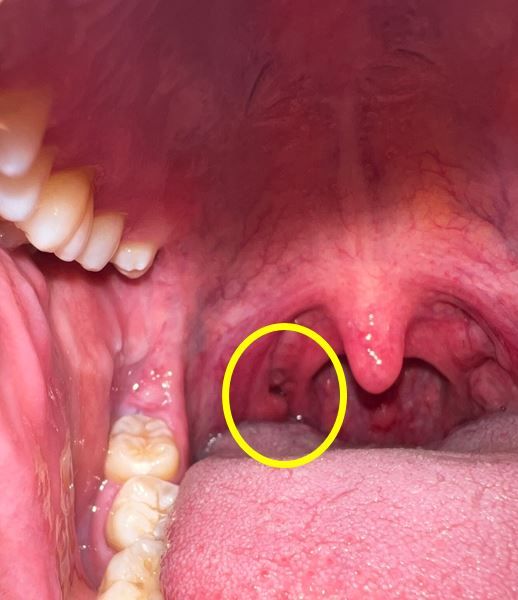

목구멍 편도 쪽에 구멍이 나있어요 이상없을까요 ?

어느순간부터 편도쪽에 이질감과 함께 편도결석의 악취가 느껴져 핸드폰으로 촬영을 해봤습니다.

확인결과 목구명 편도 쪽에(아래사진의 목구멍편도 좌측 구멍) 구멍이 있습니다.

이상없을까요 ?